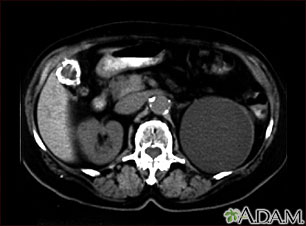

A CT scan of the upper abdomen showing a fist-sized cyst of the left kidney and gallstones (the kidney cyst was found by chance; there were no symptoms).